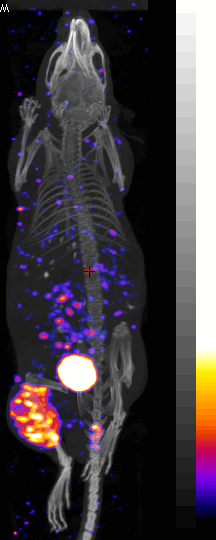

[64Cu] labeled Peptide tumor image